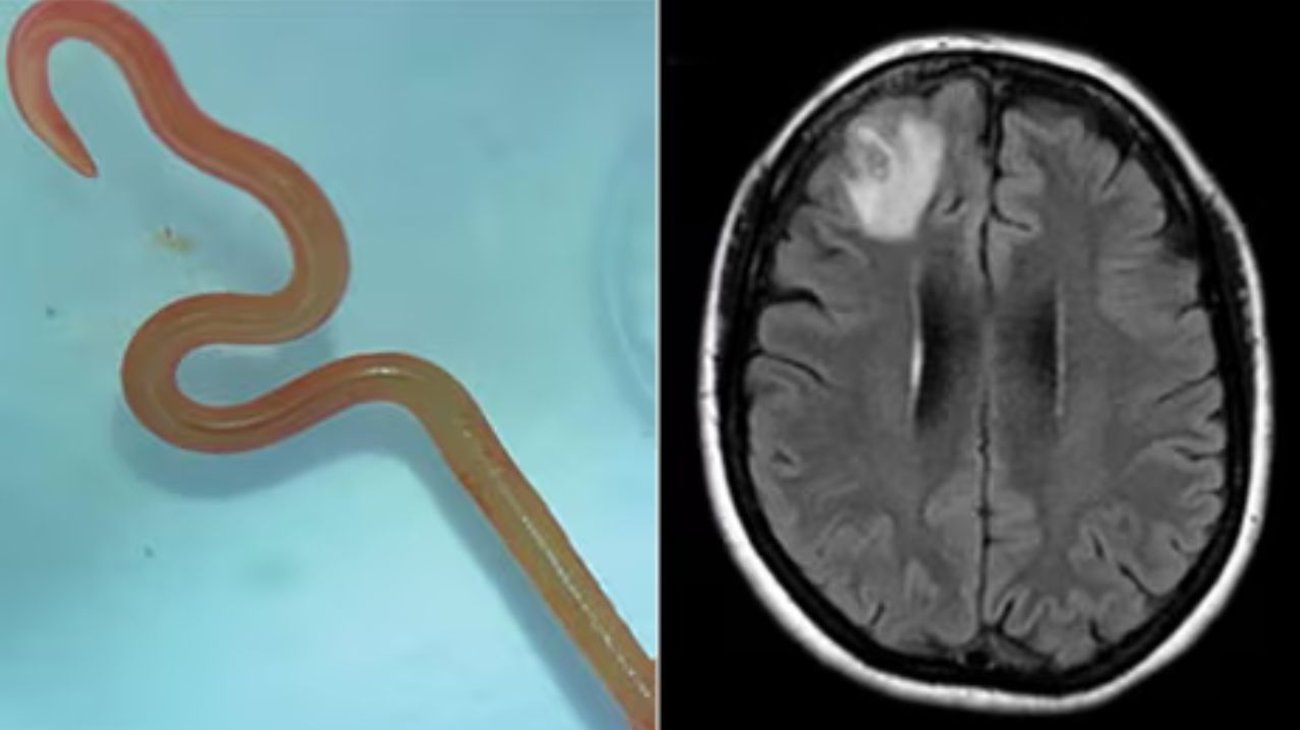

Extraen de cerebro lombriz intestinal viva de 8 centímetros

¡Impresionante!, primer caso en que neurocirujanos extraen una lombriz de 8 centímetros del cerebro de una mujer y en cualquier especie de mamífero.

Un grupo de neurocirujanos extrajeron del cerebro de una mujer australiana una lombriz intestinal viva de ocho centímetros, el primer caso de este tipo en humanos, según informaron este martes fuentes académicas.

En 2022, la paciente se sometió a una resonancia magnética tras experimentar trastornos en la memoria y depresión. Las imágenes del cerebro de la paciente revelaron que la mujer tenía una lesión atípica en el lóbulo frontal derecho.

Un neurocirujano del Hospital de Canberra exploró la anomalía y fue entonces cuando se encontró la inesperada lombriz intestinal de ocho centímetros.

El parásito fue extraído, vivo y retorciéndose, de la paciente durante de una cirugía cerebral, de la que no se precisa la fecha, y actualmente la mujer continúa siendo examinada por el equipo de especialistas en enfermedades infecciosas y cerebro.